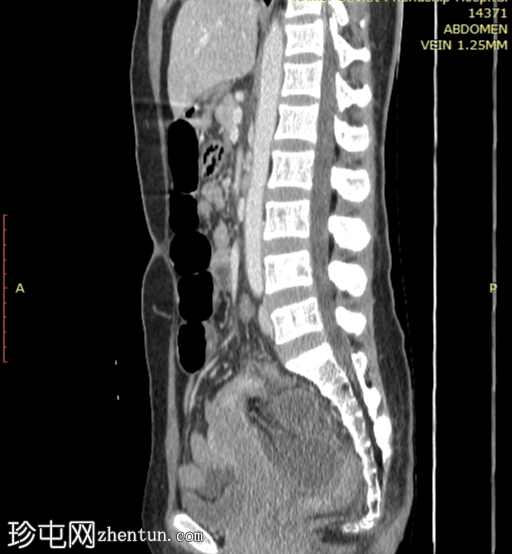

矢状位增强扫描(门静脉期)

小肠袢明显扩张,左侧附件区可见双移行点,远端回肠短段闭袢梗阻,肠颈位于左侧输卵管/左侧子宫血管附近。

肠系膜血管充血,腹盆腔可见游离液体,提示肠系膜充血。

远端回肠袢和结肠已减压。

无肠缺血或穿孔的影像学证据。